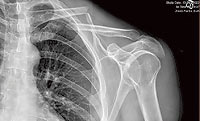

If you are like me when I had extensive oral surgery, broke my clavicle, and had orthopedic surgery, you don’t have months, weeks, or even days to recover. You’ve got plans. Whether it’s going on a trip, getting back to work, getting back on your bike, simply getting out of pain, or whatever, you don’t have time to lay in bed or sit around watching Netflix while your body does what it was designed to do.

The reason you have never heard about these tools is because they don’t involve drugs. Unlike my broken clavicle, many injuries don’t require surgery—just some cutting-edge tools we use in the office on a daily basis. Although a speedy recovery can require an investment, you don’t have to be a pro athlete to afford it. At Prestige Wellness Institute, we utilize a comprehensive approach to giving the body everything it needs to recover in a hurry.

Using these tools, I had extensive oral surgery, attended a national medical conference in another state (with a broken clavicle), then had orthopedic surgery, all in the span of six days--and did not miss a single day of work. I was back on my mountain bike—EZ’ing into it at Bar M—21 days (instead of 10 weeks) after surgery.